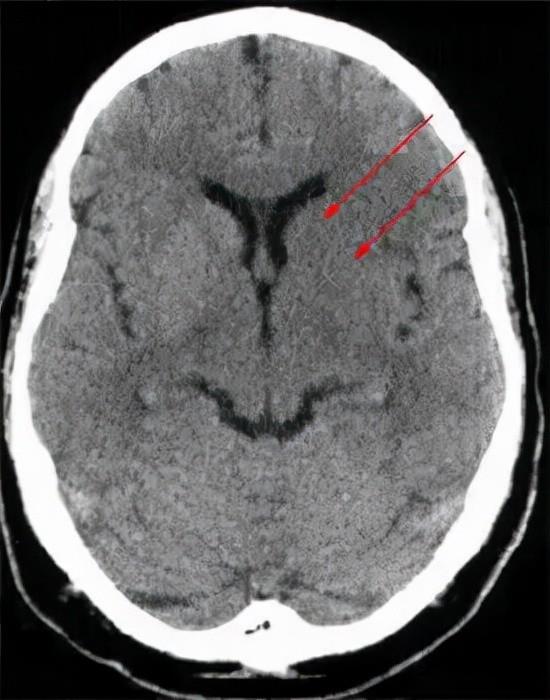

大脑中动脉高密度征是脑梗死的典型CT表现。它代表受累动脉内的血栓,一般好发于大脑中动脉起始部。CT值多在60-90 HU,呈僵硬的“杵状”影。例如,一位患者在晚上9点左右出现失语和左侧肢体无力,11点半做CT检查时发现右侧大脑中动脉高密度征,右颞叶密度较左侧稍减低。两天后复查时,右额颞叶可见片状高、等、低混杂密度影。